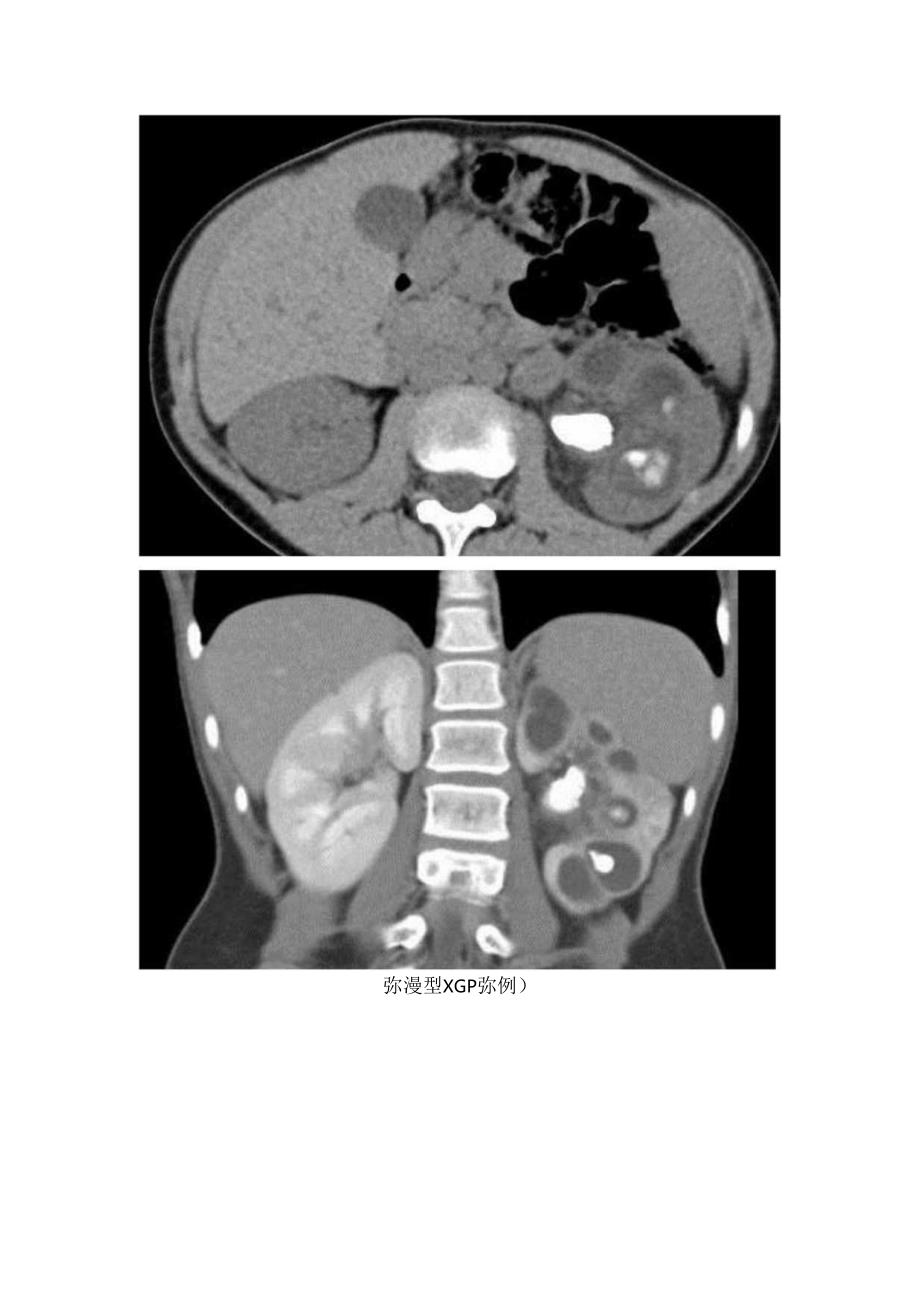

2、性肉芽肿过程,被认为是亚急性/慢性感染导致慢性但不完全免疫反应的结果。可培养出各种细菌,最常见的是大肠杆菌和奇异变形杆菌。肾脏最终被大量反应性组织取代,伴有不同程度的肾积水,其环绕在鹿角形结石(90%可见)周围。镜下可见大量泡沫(含脂质)巨噬细胞。炎症过程最终可延伸至肾周围组织,甚至邻近器官。基于相邻组织的受累程度,可分为3期:1期:病变仅局限于肾实质。2期:累及肾实质并延伸至肾周脂肪。3期:病变累及肾周和肾旁间隙或腹膜后。XGP根据病变范围分为弥漫型(9096)和局限型(1096)。前者CT表现为:1、肾实质内多发囊性占位,多以肾盂肾盏为中心,其中部分为结石梗阻所致的肾积水,部分为黄色肉芽肿

3、的脓腔。2、集合系统结石。3、肾皮质变薄。4、肾窦脂肪组织减少,多为慢性炎性反应性纤维组织增生所替代。5、肾周筋膜增厚、肾周间隙渗出积液,严重时可形成脓肿累及腰大肌。后者则表现为囊实性占位,增强后实性部分强化明显,邻近集合系统内可见结石。弥漫型XGP弥例)大体病理标本:扩张的肾盂充满大量脓液。清洗标本后,扩张的肾盏和肾盂壁增厚,有多发黄色结节。大部分肾皮质萎缩。镜下病理:黄色结节部分的切片可见泡沫状组织细胞、少量多核巨细胞和炎性细胞代替肾实质不具备典型影像表现时需与以下病变相鉴别:1、肾结核:肾集合系统狭窄与扩张并存,钙化多时表现为肾自截。2、肾脓肿。3、肾细胞癌(RCC)o4、血管平滑肌脂肪瘤(AM1.)。肾自截肾脓肿